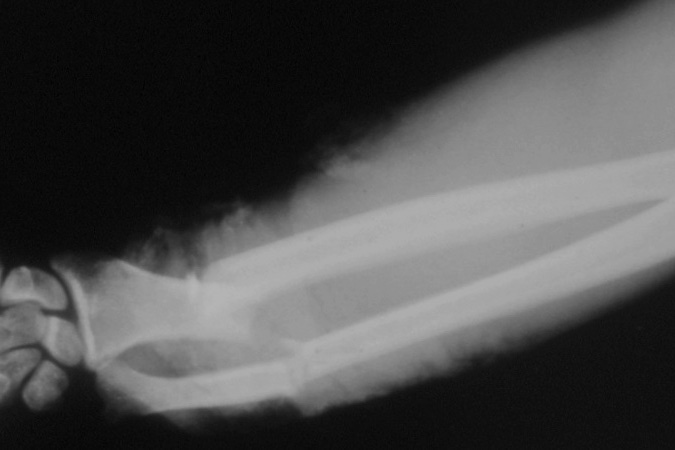

- A Monteggia fracture involves a fracture of the proximal third of the ulna combined with a subluxation or dislocation of the radial head at the PRUJ and the humeroradial joint.4,8

- These injuries most commonly occur secondary to a direct blow to the posterior aspect of the ulna, with the elbow extended and the forearm in hyperpronation.12,13

Imaging13